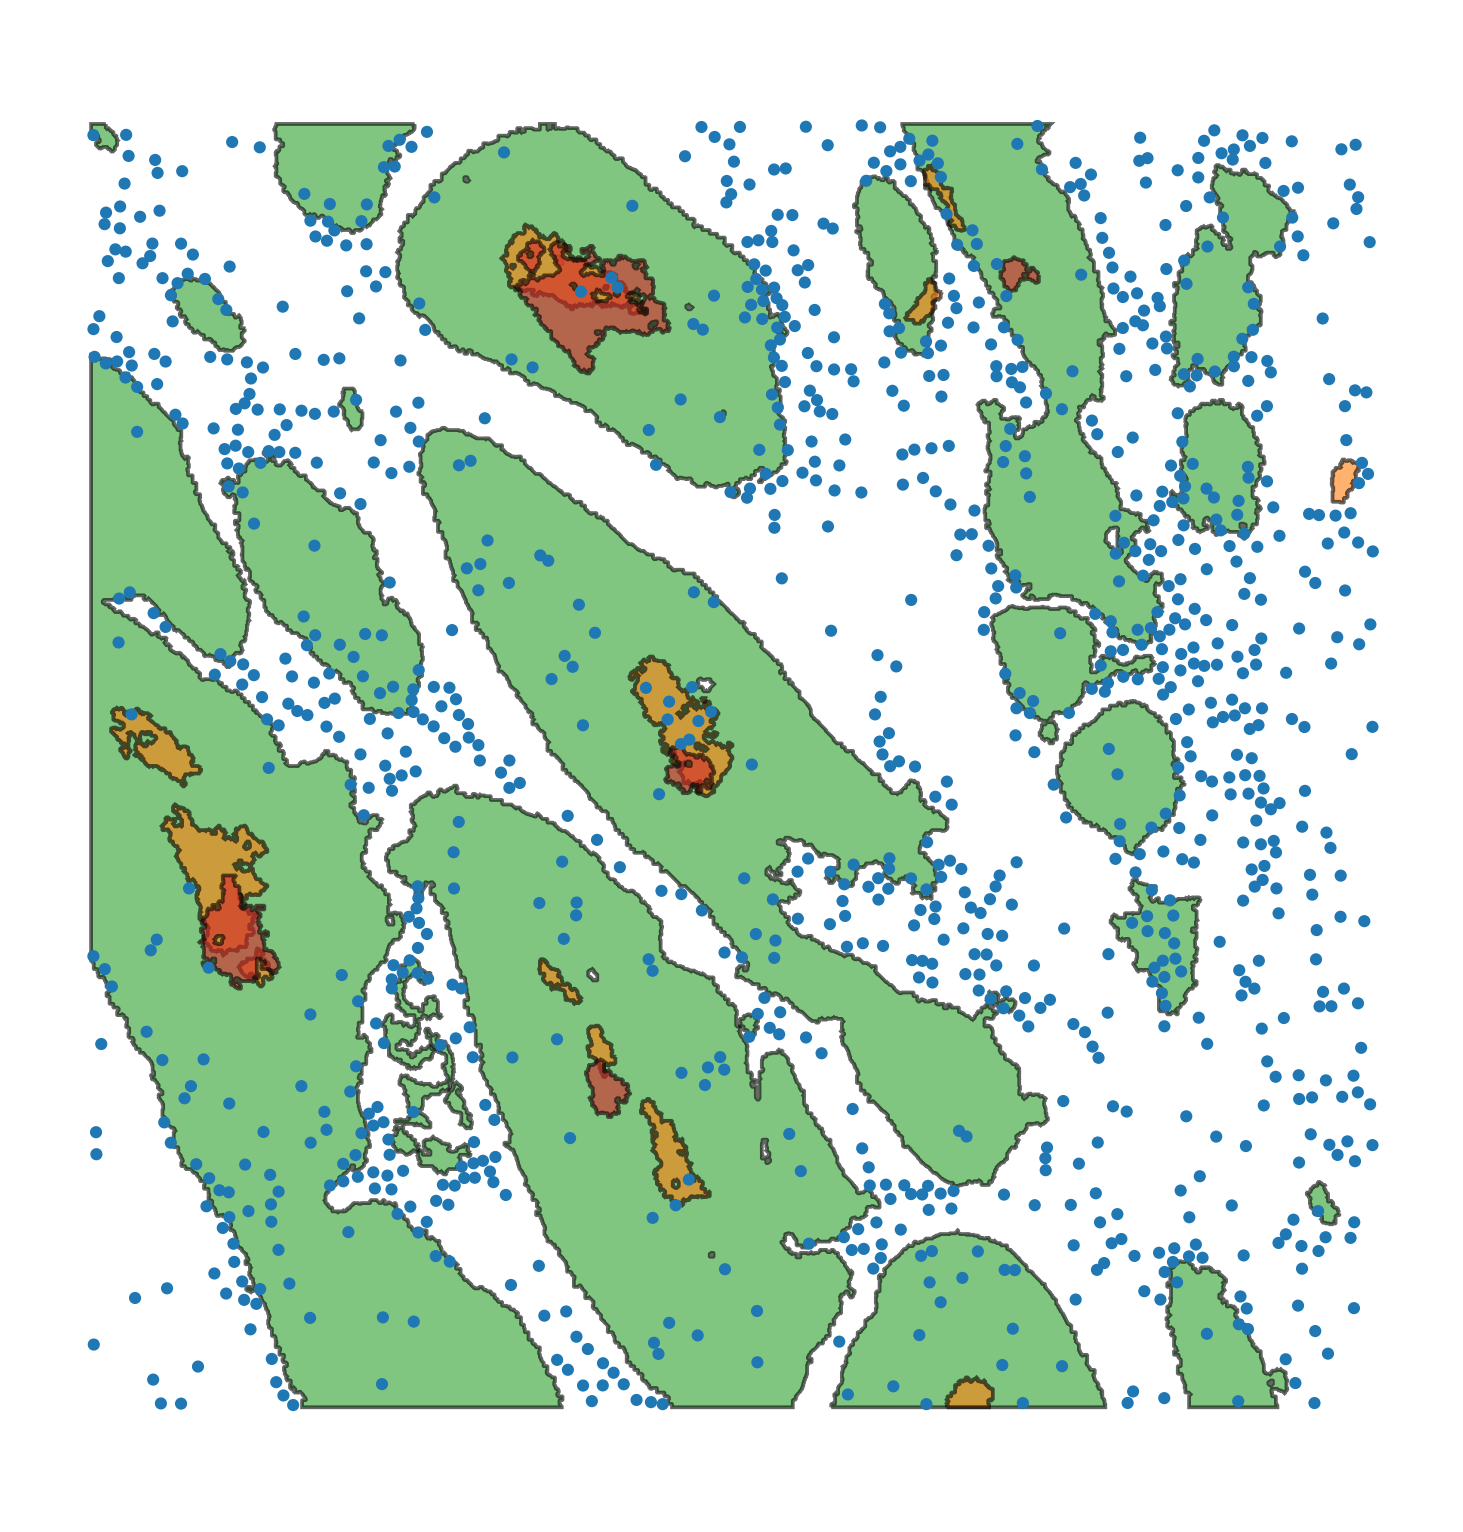

Macrophage-Hypoxia-ROI |

|

A 1.5mm square region of interest formed from a stack of aligned IHC slides in a human head and neck cancer image, see link. The domain contains cell centre locations of macrophages (CD68+), and shapes which denote boundaries of PanCK (a tumour marker), CAIX (a marker for hypoxia) and Pimonidazole (a marker for severe hypoxia). |